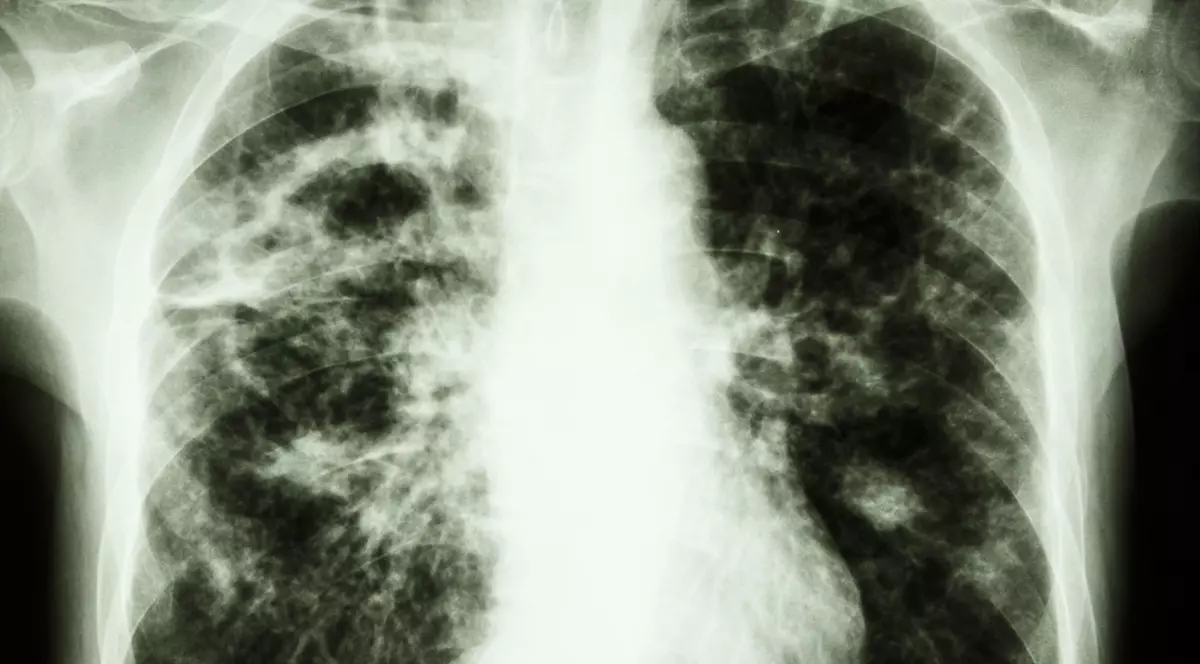

Tuberculoza se transmite prin aer, iar România are cei mai mulți bolnavi din Uniunea Europeană.